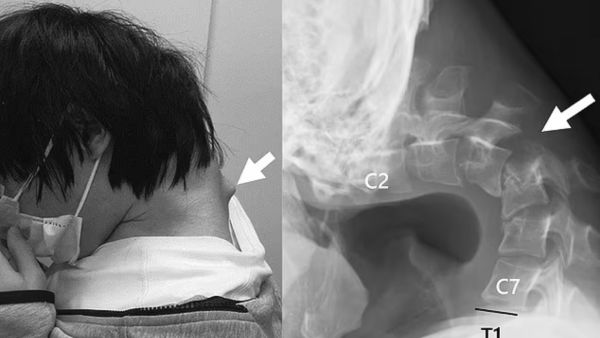

First shared by JOS Case Reports, the photos revealed and warned people that using a phone while the user's head is bent down for prolonged periods of time can result in "dropped head syndrome." X-rays of the 25-year-old Japanese man who developed a bulge extruding from his neck revealed his deformed spine.

(JOS Case Reports)